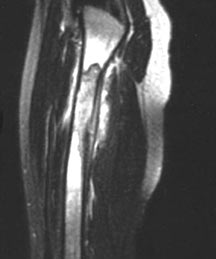

- May arise from any bone and any site within a bone (epiphyseal, metaphyseal, diaphyseal)

- Radiographically variable appearance: may appear benign (geographic) or malignant (permeative or moth eaten)

Sites:

- Femur